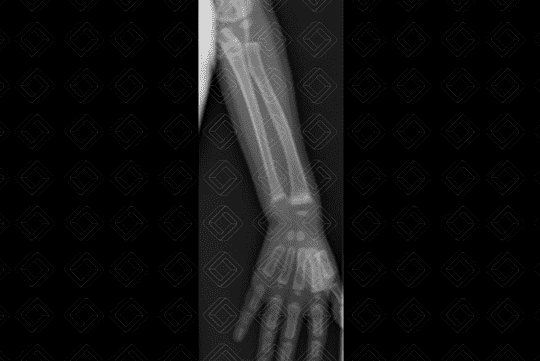

Descrição da lesão: Radiografia dos membros superiores e mãos (figuras 1 e 2). Alargamento das fendas epifisárias e metafisárias da ulna e rádio, bilateralmente. As metáfises apresentam aspecto franjeado. Osteopenia difusa. Estes achados radiológicos são típicos do raquitismo.